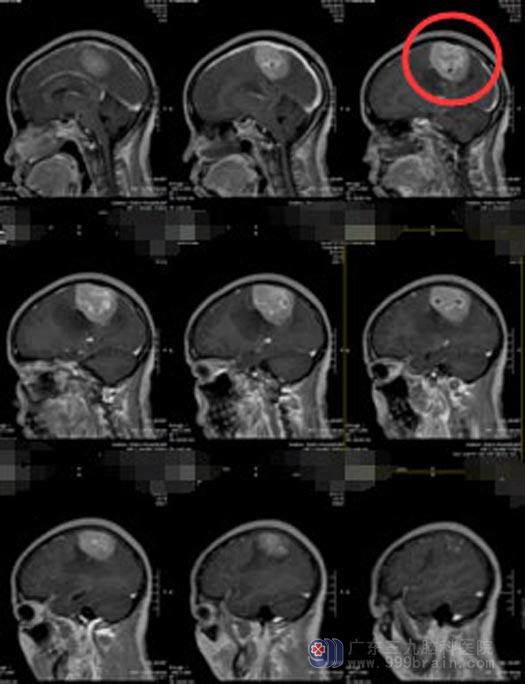

广东三九脑科医院进一步头颅MR检查显示:右侧额顶部镰旁占位性病变,大小约5.23cm×4.11cm×4.68cm,相应处上矢状窦位变窄,考虑肿瘤压迫所致,脑膜瘤可能。

由综合神经外科鲁明主任主刀,在全麻下行“右侧顶部镰窦旁巨大占位性病变切除手术”,术中见肿瘤侵犯上矢状窦,呈灰白色,质地中,血运丰富,显微镜下全切肿瘤,上矢状窦保护完好。术后潘女士恢复良好,已康复出院。病理提示:纤维型脑膜瘤,WHO I级。

手术前